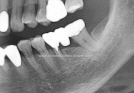

Clinical Cases

• Case1

• Case2

• Case3

• Case4

• Case5

• Case6

• Case7

• Case8

• Case9

• Case10